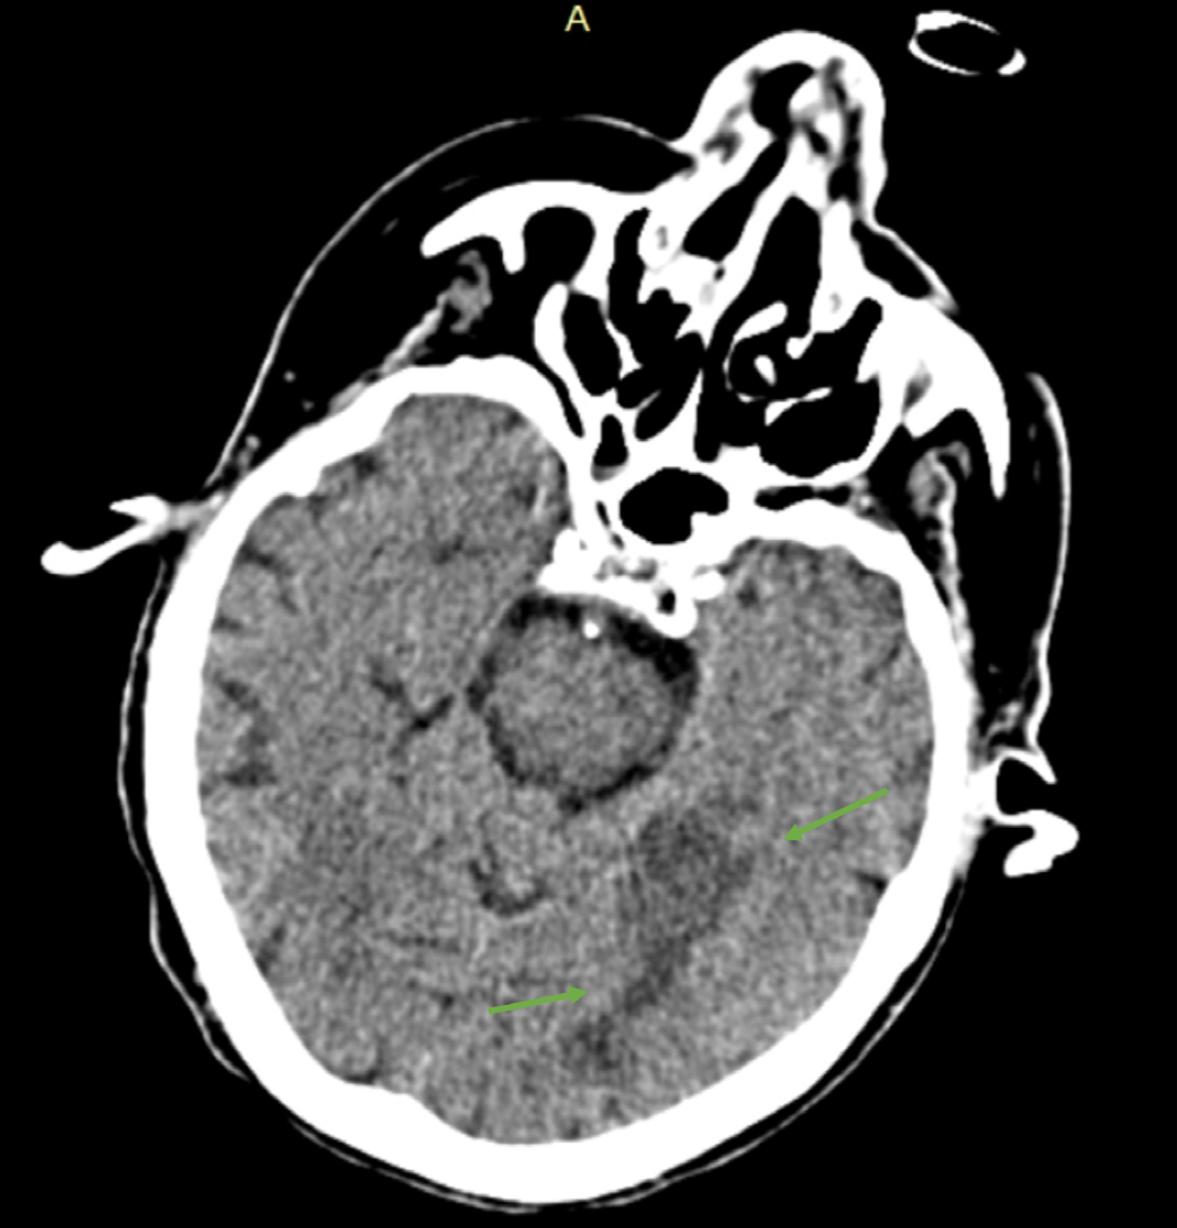

Computed tomography of the brain showing (A) frontal intraparenchymal cerebral hemorrhage and perilesional edema in transversal view; (B) subarachnoid hemorrhage in sagittal view; and (C) frontal intraparenchymal hemorrhage in frontal view. The arrows indicate (A) a 17 mm frontal hematoma with peri-hemorrhagic edema; (B) left parietal subarachnoid hemorrhage; and (C) frontal hematoma.